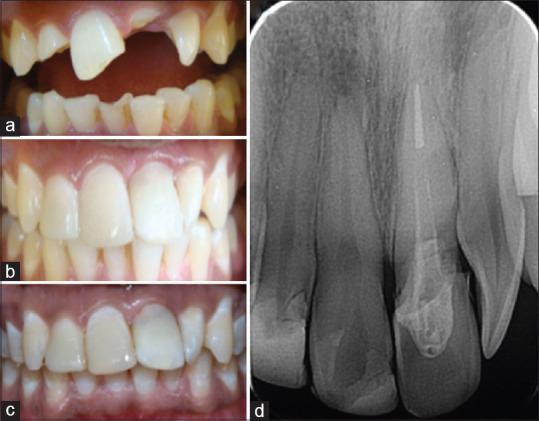

Anterior teeth fracture is a common form of dental trauma that mainly affects children and adolescents. Maxillary incisors are the most commonly affected teeth. Loss of coronal tooth structure might affect esthetics and function. In recent decades, dentistry has shown many scientific and technological advances in restorative materials. However, no synthetic restorative material can replicate the natural tooth structure. Hence, the use of natural tooth as a restorative material has been suggested in literature and is termed as a biological restoration. The present case report represents the successful use of biological post and crown and was adequate with respect to adhesion, function, and esthetics with the follow-up period of 1 year. Hence, it may be concluded that the biological restoration, if feasible, is a cost-effective way to restore a damaged tooth with acceptable esthetics and tooth functions in the stomatognathic system.

前牙折断是一种常见的牙外伤形式,主要影响儿童和青少年。上颌切牙是最常受影响的牙齿。牙冠结构的丧失可能会影响美观和功能。近几十年来,牙科在修复材料方面取得了许多科学技术进步。然而,没有一种合成修复材料能够复制天然牙齿结构。因此,文献中建议使用天然牙齿作为修复材料,这被称为生物修复。本病例报告展示了生物桩核冠的成功应用,在1年的随访期内,其在粘结、功能和美观方面均表现良好。因此,可以得出结论,如果可行,生物修复是一种在口腔颌面部系统中以可接受的美观和牙齿功能修复受损牙齿的经济有效的方法。